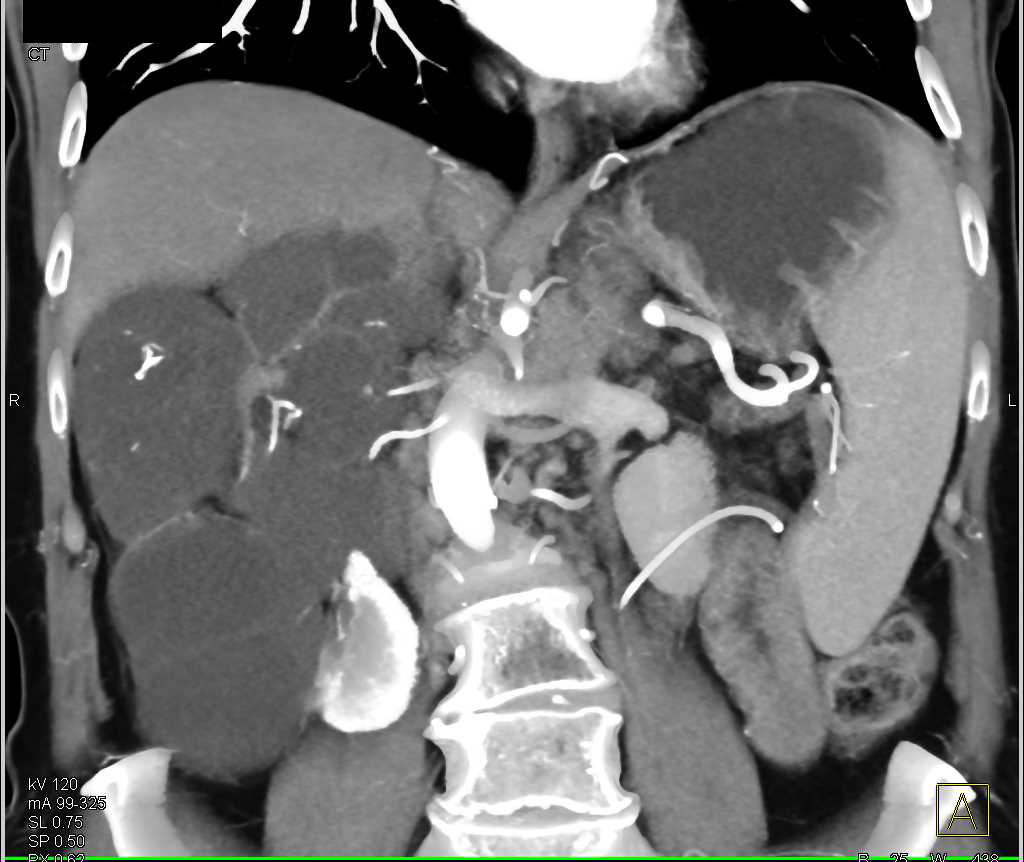

Mixed Epithelial Stromal Tumor (MEST) Kidney